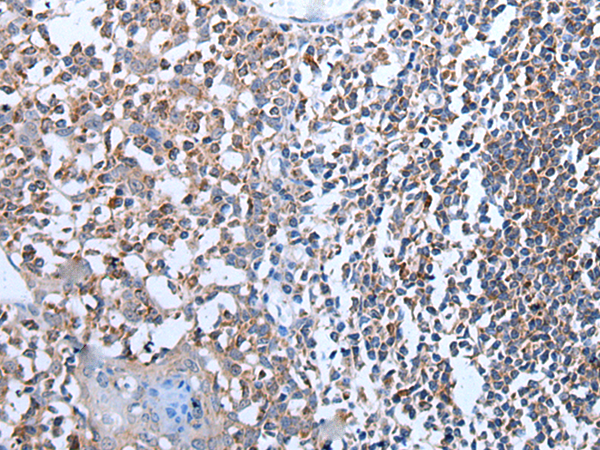

The image is immunohistochemistry of paraffin-embedded Human esophagus cancer tissue using P12848(NOS3 Antibody) at dilution 1/35. (Original magnification: ×200) |

The image is immunohistochemistry of paraffin-embedded Human tonsil tissue using P12848(NOS3 Antibody) at dilution 1/35. (Original magnification: ×200) |